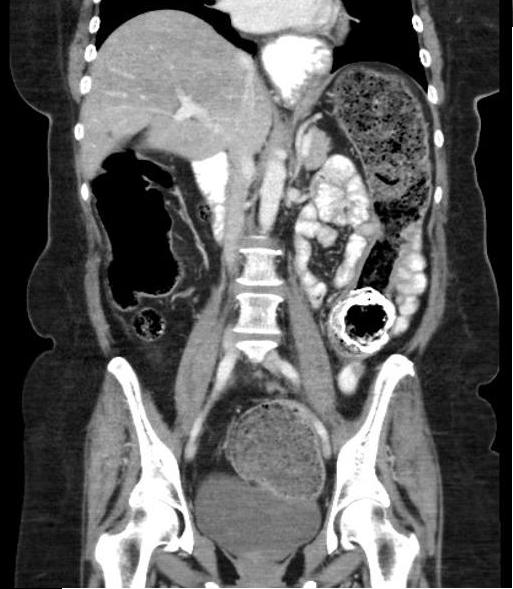

Colo occusion par les fecalomes :

Le colon est tres dilate et la partie inferueure est

remplie par des fecalomes en image iso-dense a non

homogene . |

|

L'occlusion du colon a cause

fecalomes . Le colon est tres dilate et

image de fecalome est en iso-dense non homogene a

inferieure du colon sigmoide du rectum. |